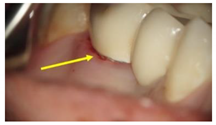

GroupDescription Clinical Presentation

Group-I (n = 35)Received a conventionally fabricated cobalt-chrome (Co-Cr) ceramic prosthesis; conventional wax up copings were converted to metal copings by the lost wax technique followed by porcelain layering.Molecules 26 01331 i001

Group-II (n = 30)Received a Co-Cr ceramic prosthesis fabricated by a computer-aided design and computer aided manufacturing (CAD/CAM) using Sintron technology. Copings were milled from a soft pre-sintered Co-Cr alloy by CAD/CAM, sintered in a special oven and followed by porcelain layering.Molecules 26 01331 i002

Group-III (n = 30)Received zirconia-based prostheses fabricated by the CAD/CAM technique. Zirconia was milled using the CAD/CAM system from pre-sintered zirconia blocks, sintered, and followed by porcelain layering.Molecules 26 01331 i003

Arrows show the crown margins and gingival tissues interface.